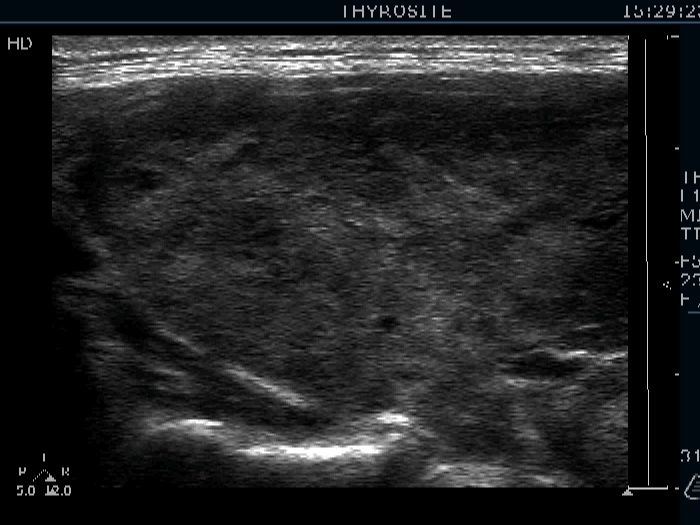

Consecutively operated patients with autoimmune thyroid disease - case 17 (1573) (ultrasonographic picture 2)

Right lobe, longitudinal view.